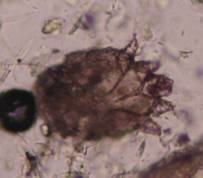

CBC基本正常;皮肤搔刮镜检:在耳缘增厚处及肘部病变处滴甘油静置

10min,捏挤待搔刮的皮肤,用不锋利的手术刀片对病变皮肤进行搔刮,必要时搔刮至少量渗血为止,搔刮多次,在显微镜下观察有无异常。后对取样的病变皮肤进行局部清理消炎。

进行

5

次搔刮,在显微镜视野中明显见一疥螨虫体,诊断为犬疥螨感染。